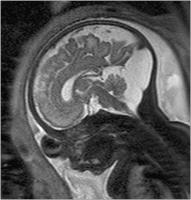

Abbildung 2a-b: SSW 30, Fetus mit Balkenagenesie, A. Medianes Schnittbild: Fehlender Balken, radiäre Gyrierung an der Medialfläche der Hemisphäre. Der Aquädukt und die Vierhügelplatte unauffällig. Der Hirnstamm zeigt dorsal dünklere Signale als ventral, was der normalen, dort bereits in dieser SSW vorhandenen Myelinisierung entspricht. Im Profil geringe Retrognathie. B. Frontales Schnittbild. Typische Konfiguration der Seitenventrikel, die auf Grund der medial der Vorderhörner erkennbaren Probst’sche Bündel weit auseinander stehen. In den erweiterten Temporalhörnern erkennt man eine nahezu senkrecht stehende Hippocampusformation, was einer Malrotation entspricht. Die Gyrierung ist symmetrisch, eine pathologische Konfiguration des frontalen Anteils des Gyrus cinguli, wie sie im Rahmen der Balkenagenesie zu erwarten ist, besteht. Intrazerebral ist die zelldichtere und daher dünklere Stammganglienregion von der helleren weißen Substanz, die ebenfalls in entwicklungsbedingt unterschiedliche Graustufen gegliedert ist, abgrenzbar.